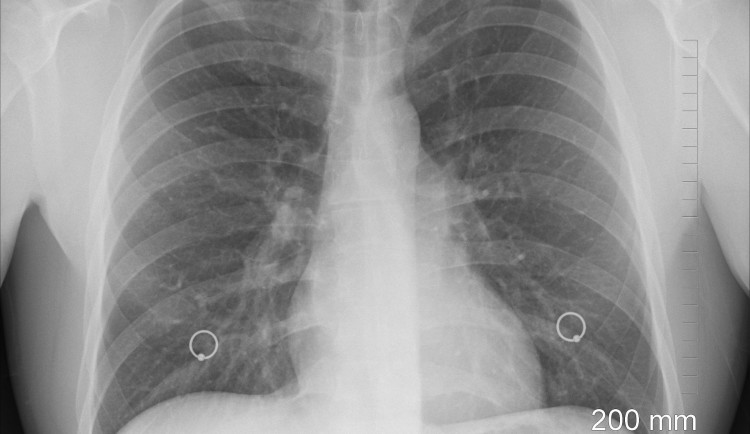

Rekord v pražské Všeobecné fakultní nemocnici. Pacientku udrželi na umělé plíci 143 dní

Všeobecná fakultní nemocnice se tento týden zapsala do zdravotnických statistik. Lékaři z pražské nemocnice dokázali udržet pacientku na umělé plíci 143 dní. Světový rekord byl do té doby 79 dní. První český bypass obcházející plíce zachránil...